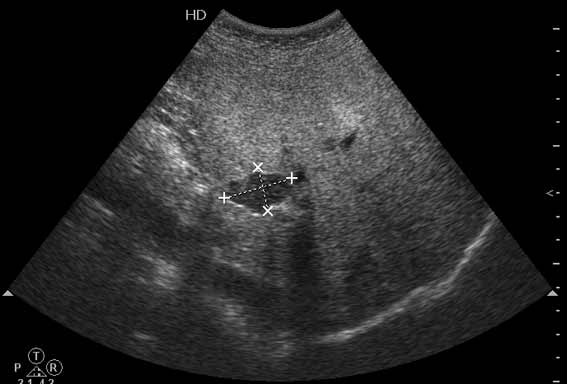

В печени выявлен гипоэхогенный очаг неокруглой формы, аваскулярный при цветовой доплерографии.

Простая и одновременно "сложная" задачка. По УЗИ; явный стеатоз печёночной паренхимы (теперь ключевые слова); на ФОНЕ СТЕАТОЗА определяется гипоэхогенное образование. Варианты? Очаговое образование; и менее вероятно участок гипостеатоза (но не похоже, есть чёткие границе, + не та локализация).